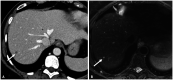

Photon-counting detector (PCD) CT is a new CT technology utilizing a direct conversion X-ray detector, where incident X-ray photon energies are directly recorded as electronical signals. The design of the photon-counting detector itself facilitates improvements in spatial resolution (via smaller detector pixel design) and iodine signal (via count weighting) while still permitting multi-energy imaging. PCD-CT can eliminate electronic noise and reduce artifacts due to the use of energy thresholds. Improved dose efficiency is important for low dose CT and pediatric imaging. The ultra-high spatial resolution of PCD-CT design permits lower dose scanning for all body regions and is particularly helpful in identifying important imaging findings in thoracic and musculoskeletal CT. Improved iodine signal may be helpful for low contrast tasks in abdominal imaging. Virtual monoenergetic images and material classification will assist with numerous diagnostic tasks in abdominal, musculoskeletal, and cardiovascular imaging. Dual-source PCD-CT permits multi-energy CT images of the heart and coronary arteries at high temporal resolution. In this special review article, we review the clinical benefits of this technology across a wide variety of radiological subspecialties.